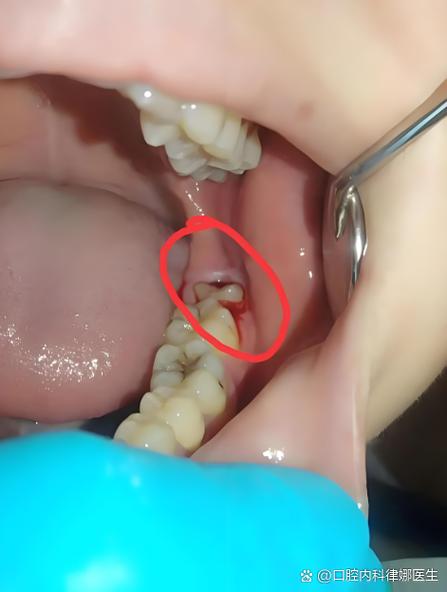

智齿引发的最常见疾病是智齿冠周炎,主要发生在智齿部分萌出或完全未萌出时,牙冠周围软组织发生的炎症,由于智齿萌出不全,牙冠表面覆盖的牙龈瓣与牙冠之间形成盲袋,食物残渣和细菌容易在此积聚,当身体抵抗力下降或局部受到刺激时(如感冒、疲劳、局部创伤等),便容易引发急性炎症,患者会感到牙龈红肿、疼痛,严重时可能伴有张口受限、吞咽困难、发热、头痛等全身症状,甚至可能发展为颌面部间隙感染,对健康造成严重威胁,对于反复发作的智齿冠周炎,拔除病灶牙是最根本的治疗方法。

智齿对邻牙的影响也不容忽视,当智齿位置不正,尤其是近中阻生时,其牙冠可能会顶在邻牙(通常为第二磨牙)的颈部,导致邻牙发生远中邻面龋坏,这种龋坏位置隐蔽,早期不易发现,往往进展到牙髓甚至根尖周时才会出现症状,治疗难度大,严重时甚至可能导致邻牙丧失,智齿与邻牙之间容易形成“食物嵌塞”,长期嵌塞会刺激牙龈,引发牙周炎,导致牙槽骨吸收和牙龈萎缩,影响邻牙的稳固性,当智齿对邻牙造成潜在威胁时,医生通常会建议尽早拔除,以保护邻牙的健康。